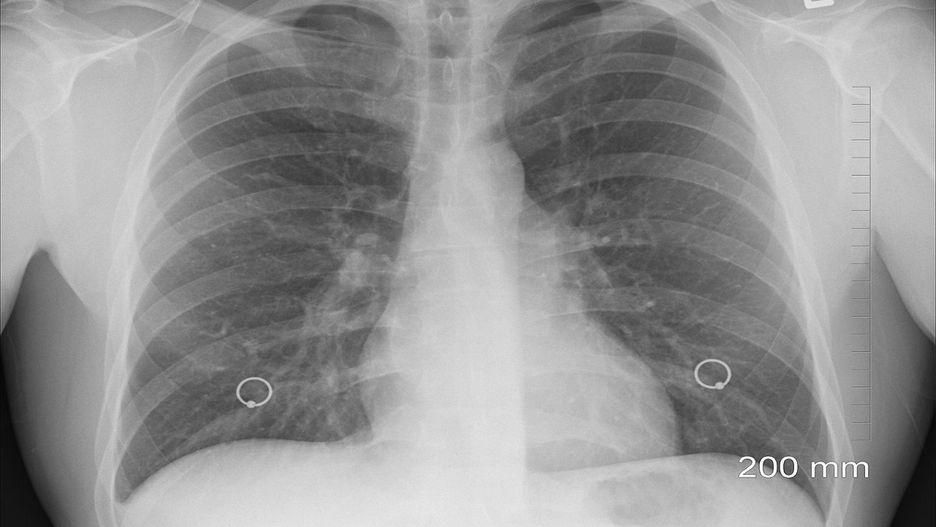

Źródło zdjęć: © Pixabay

Gruźlica to bakteryjna choroba infekcyjna. Najczęściej atakuje płuca ze względu na panująca korzystne dla bakterii warunki do życia. Zdarza się też, że objawia się zmianami na skórze, w kościach, mózgu czy węzłach chłonnych.